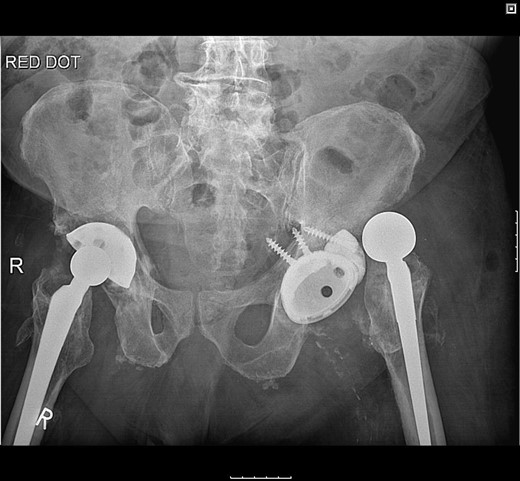

The patient was subsequently scheduled for revision surgery of the acetabular component. Intraoperatively, there was blackening of the periprosthetic tissue and metal debris throughout. The PE liner remained engaged within the acetabular cup with significant wear through its back. The femoral head had migrated superolaterally through the acetabular cup and was articulating with the superior acetabular wall causing bony destruction. The acetabular cup remained well fixed within the acetabulum with good bony ingrowth (Figs 2 and 3).

The acetabular component showing extreme wear-through and metallic fragments.